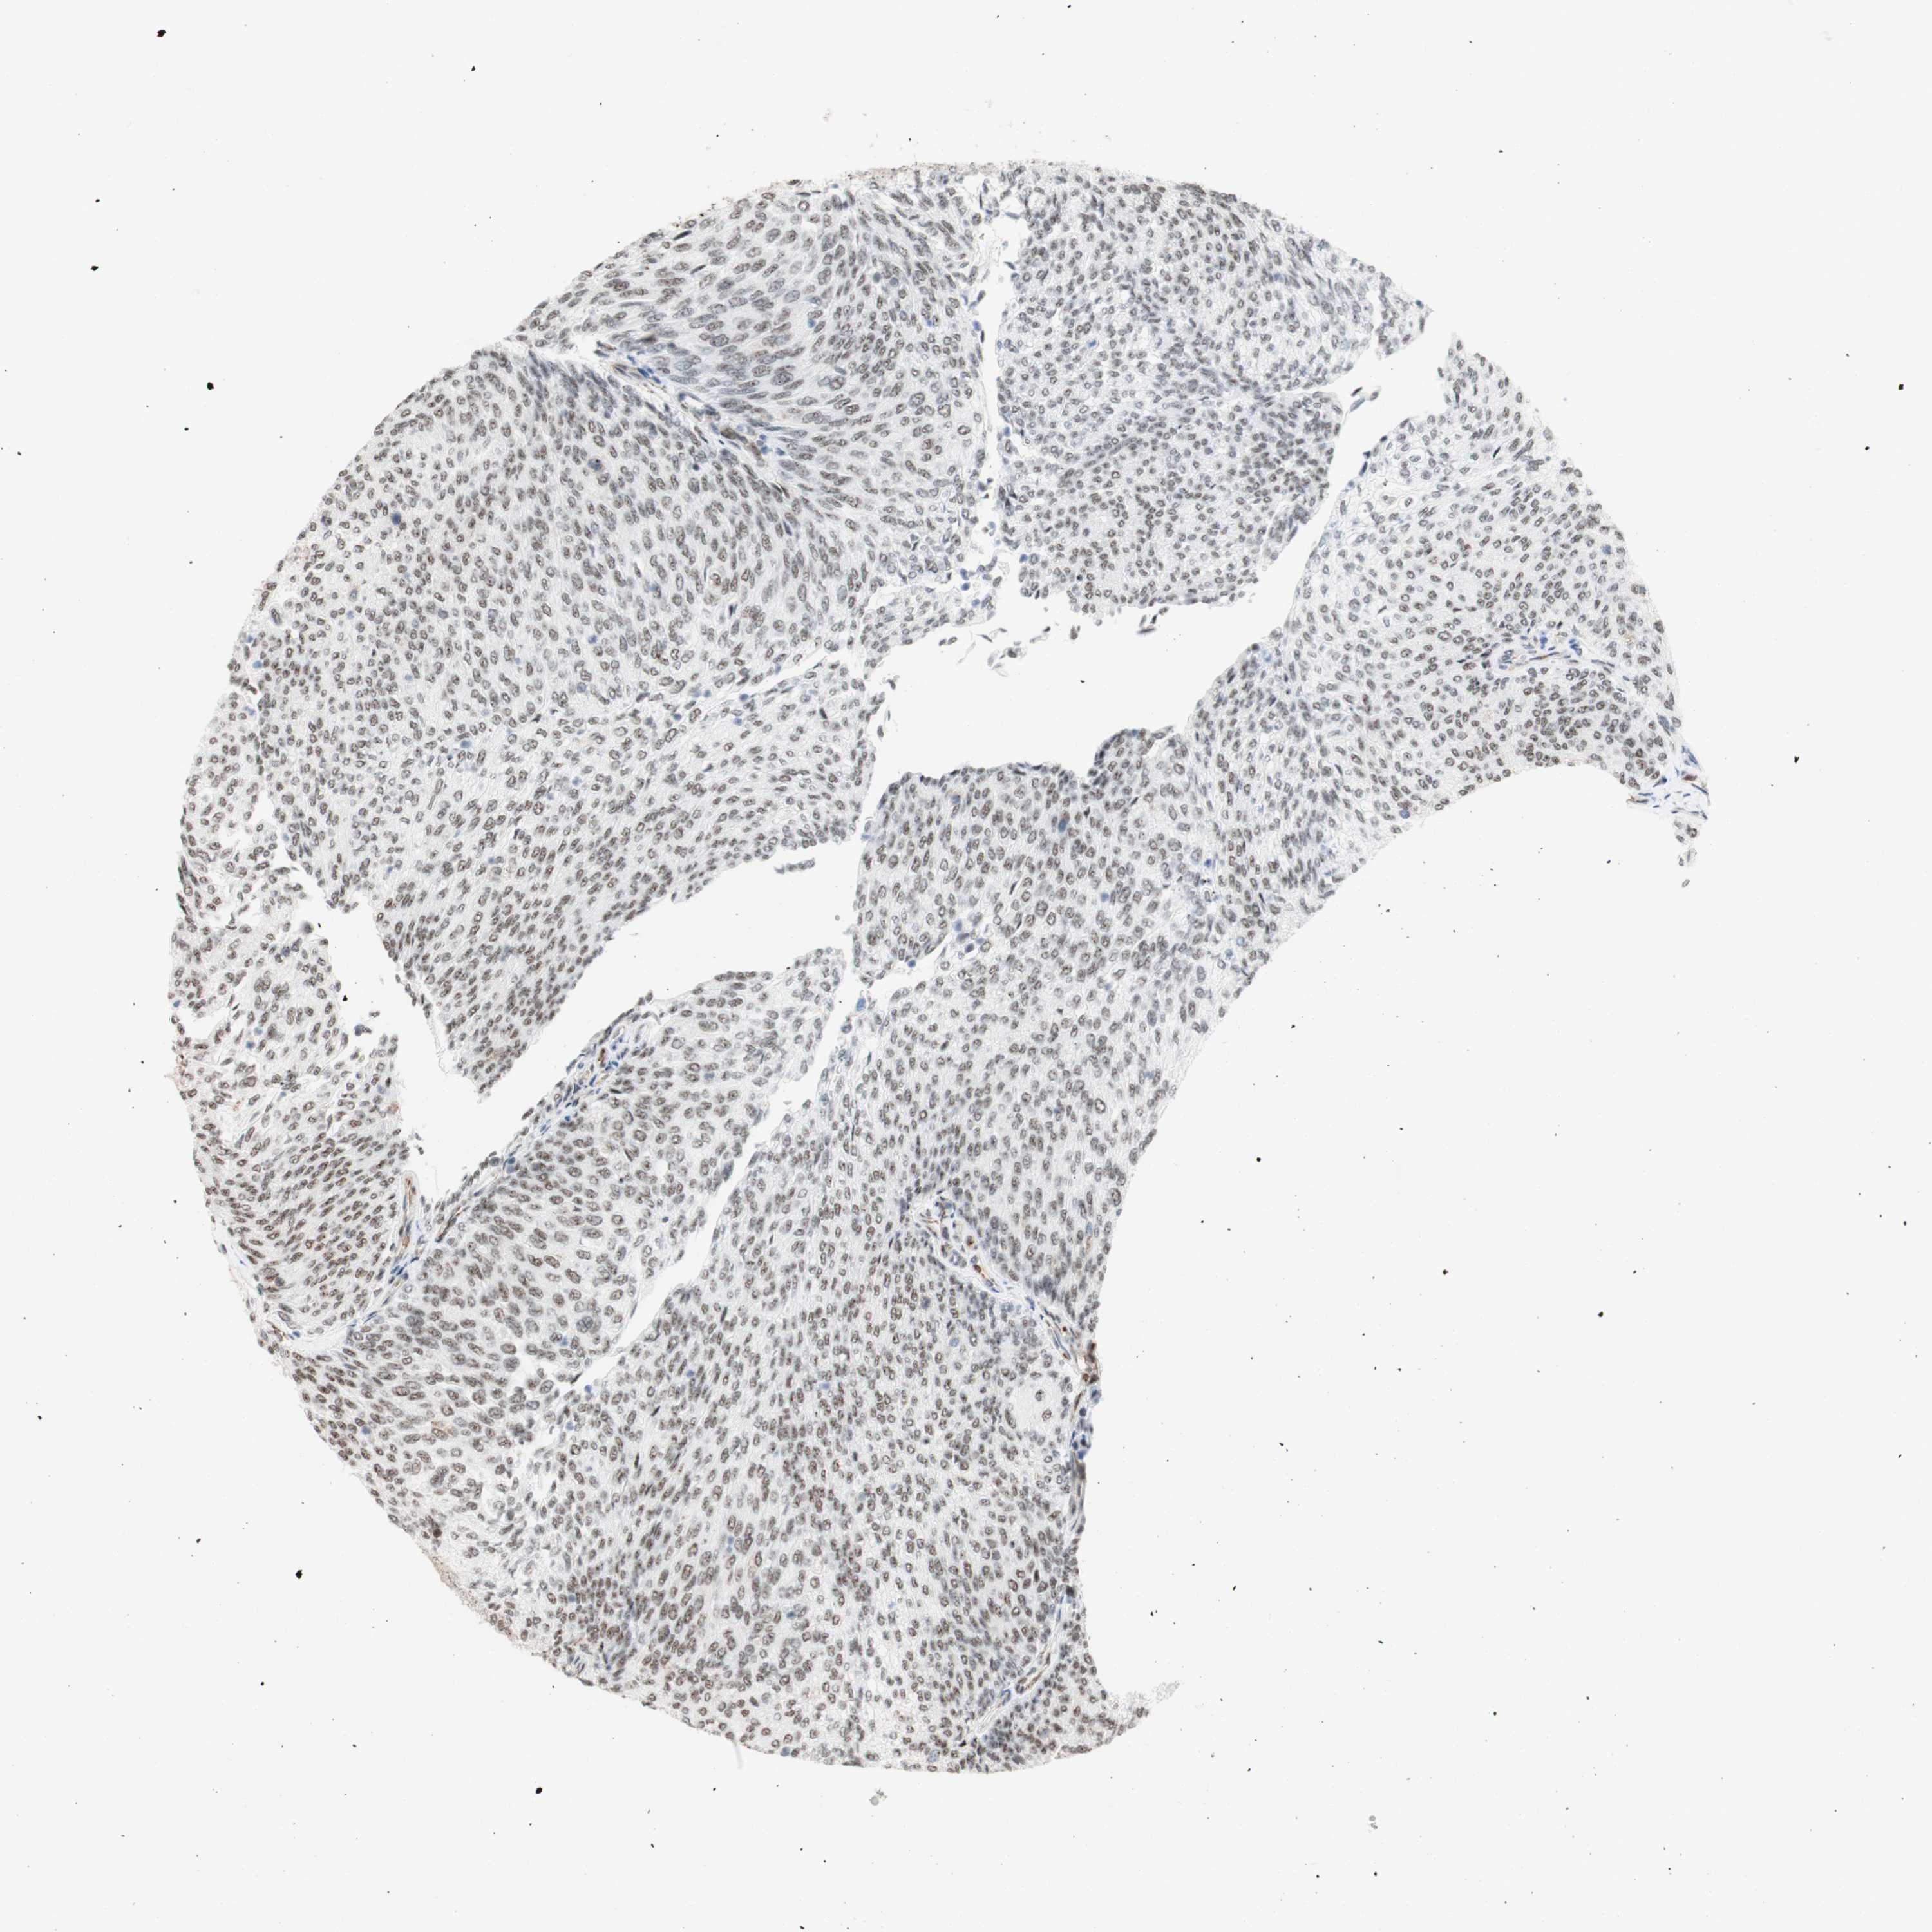

UROTHELIAL CANCER - Protein expressioni

A mouse-over function shows sample information and annotation data. Click on an image to view it in a full screen mode. Samples can be filtered based on level of antibody staining by selecting one or several of the following categories: high, medium, low and not detected. The assay and annotation is described here.

Note that samples used for immunohistochemistry by the Human Protein Atlas do not correspond to samples in the TCGA dataset.

Antibody stainingi

Antibody staining in the annotated cell types in the current human tissue is reported as not detected, low, medium, or high, based on conventional immunohistochemistry profiling in selected tissues. This score is based on the combination of the staining intensity and fraction of stained cells.

Each image is clickable and will lead to virtual microscopy that enables deeper exploration of all samples and also displays staining intensity scores, fraction scores and subcellular localization as well as patient and tissue information for each sample.

Antibody HPA011352

Antibody CAB012273

Staining

High

Medium

Low

Not detected

Intensity

Strong

Moderate

Weak

Negative

Quantity

>75%

75%-25%

<25%

None

Location

Nuclear

Cytoplasmic/membranous

Cytoplasmic/membranous,nuclear

Urothelial carcinoma, Low grade

Urothelial carcinoma, High grade